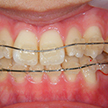

8. 矯正中正面

ジスキングには細心の注意を払い、矯正装置を装着したところです。ちなみに上顎の歯列拡大(少ししか拡大できなかったが)で、下顎左側の2,3番間の叢生が若干ですが改善しています。